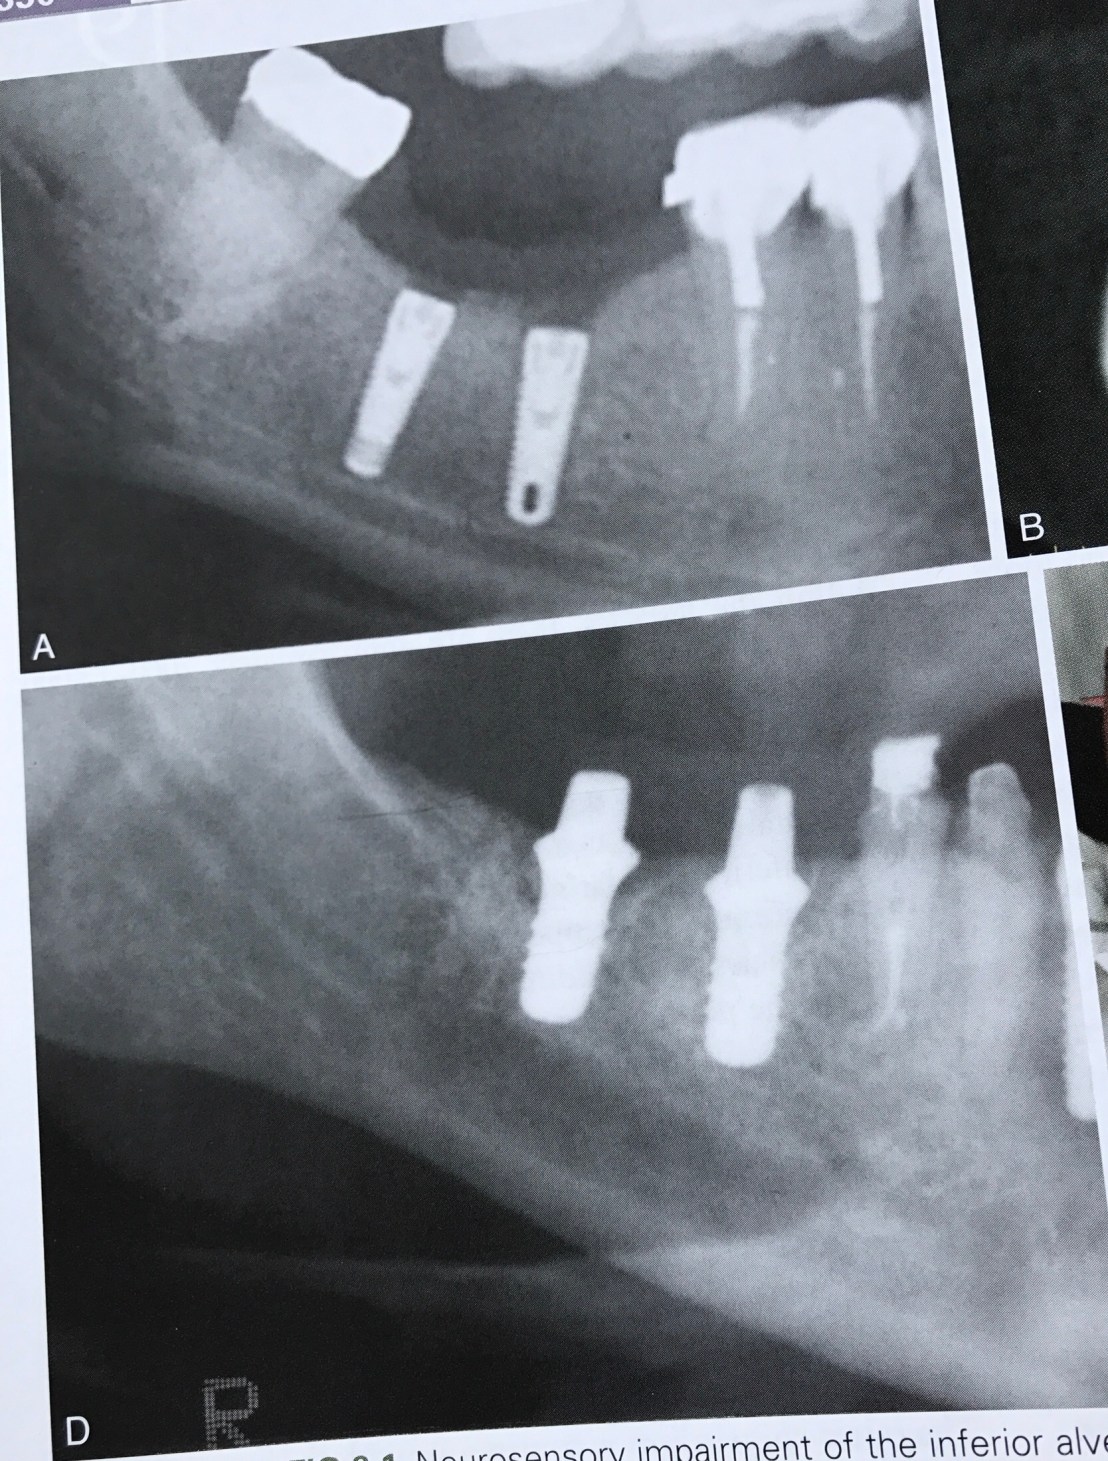

บทที่ 9 อาการชาที่เกิดจาก Implant

จุดประสงค์ของบทนี้คือ การป้องกันอาการชาครับ

Film แสดงการวางตำแหน่ง Implant ที่ลึก (เทียบระดับ CEJ) และปลายที่รบกวน Mand canal

ถ้ามอง Cross section view ในรูป B รูเปิดที่เห็นด้าน buccal นั่นคือ Mental foramen ครับ

รูป E ภาพ CBCT แสดงการยืนยันชัดเจน